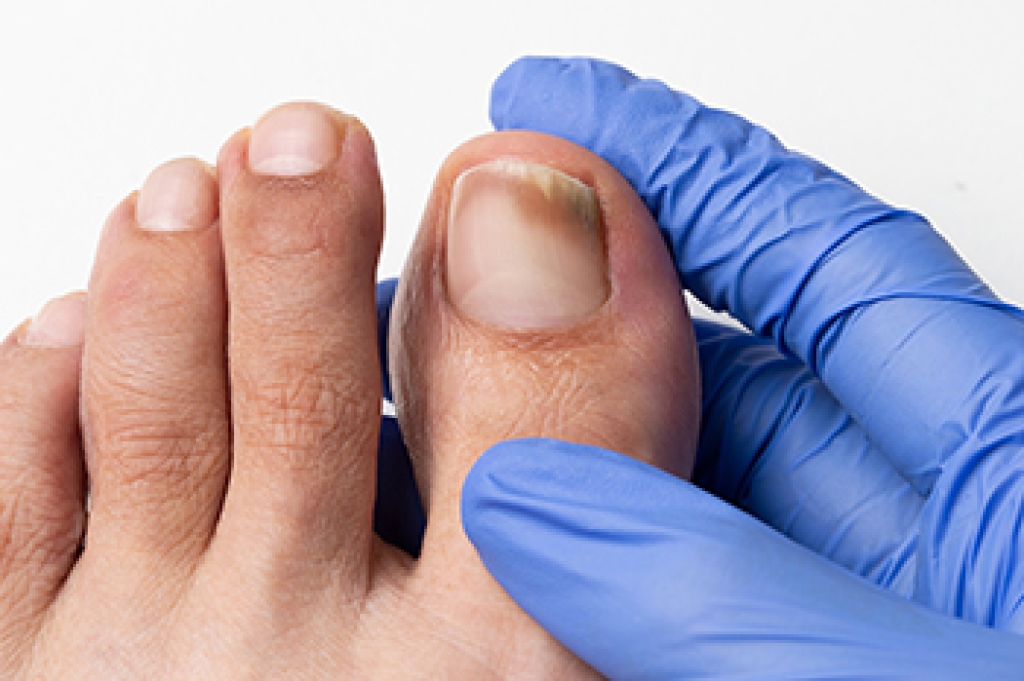

- Nail Injury

Although the injured toe should be monitored daily, it is especially important to have a podiatrist look at your toe if you have severe symptoms. Some of these symptoms include worsening or new pain that is not relieved with medication, sores, redness, or open wounds near the toe.